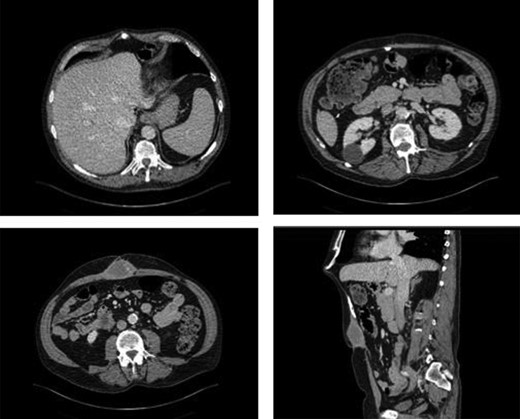

A 65 year-old male was suffering from chronic abdominal pain and foreign body sensation following incisional hernia repair with mesh in 2010. In March 2010, the patient underwent an open right hemicolectomy for benign multiple colonic polyps and subsequently developed an incisional hernia. In November 2010, he underwent open incisional hernia repair with an onlay Prolene mesh. Subsequent to the mesh repair, he had sharp pain in the epigastric area particularly when bending forward and fullness in his upper abdominal region. He was referred to the outpatient general surgery clinic at a tertiary level hospital for an assessment. On focused abdominal exam, he had a midline laparotomy incision with no acute signs of infection. There was fullness superior to his umbilicus with a palpable subcutaneous mass measuring approximately 6 cm in diameter. Cross sectional imaging revealed an ovoid collection in the anterior abdominal wall, measuring 4.4 × 8 cm on magnetic resonance imaging (MRI) and 3.3 × 5.4 cm on computed tomography (CT). In addition, an abnormal calcification superior to the collection could be appreciated on CT (Fig. 1). These findings were suggestive of a chronic hematoma and scar tissue. The patient agreed to undergo debridement of chronic hematoma and partial mesh excision. Intraoperatively, the ovoid collection was approached via a midline incision and was encountered after dissection through the subcutaneous tissue. It was comprised of a thick rind of scar and fibrous tissue, measuring approximately 8 × 8 cm. It was unroofed, with immediate expression of old hematoma as well as fibrous tissue. Part of the overlying Prolene mesh and thick scar tissue were excised. The remainder of the Prolene mesh was well incorporated to his fascia and left in place. As the superior aspect of the collection was dissected out by entering deep to the fascia, a piece of calcified tissue was dissected out from the preperitoneal space superior to the mesh. It was suspected to be heterotopic ossification, and it was removed (Fig. 2). The fascia was then primarily repaired, and then the incision was closed in layers after thorough irrigation. On postoperative follow-ups in the clinic at 2 and 6 weeks, the patient was doing well, and his pain had improved significantly.

Intraoperative finding of the abnormal calcified tissue below the xiphoid process.